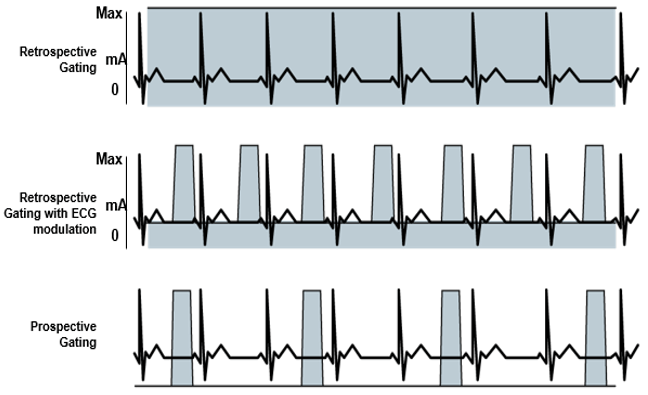

Gating

You should first understand the basics of helical CT. The main challenge in cardiac CT is temporal resolution – in other words, imaging fast enough to ‘freeze’ the motion of the heart. If you are too slow (or image at the wrong time), your images will be blurred by the contraction of the heart.

Gating techniques are used to improve temporal resolution and minimize imaging artifacts caused by cardiac motion. Two approaches to cardiac gating are typically used: prospective ECG triggering and retrospective ECG gating. The least cardiac motion occurs during diastole when the ventricles are passively filling.

In addition to imaging with high temporal resolution, we must image at the correct time – in synchrony with the cardiac cycle. There are two methods of accomplishing this: prospective and retrospective ECG gating. Prospective gating, or prospective ECG triggering, only acquires images during the cardiac diastole; the scanner simply waits in between.

Retrospective gating acquires images continually throughout the cardiac cycle and simply pieces together images from the desired phase (typical diastole for anatomic imaging) after the entire scan is completed. There are advantages and disadvantages to each.